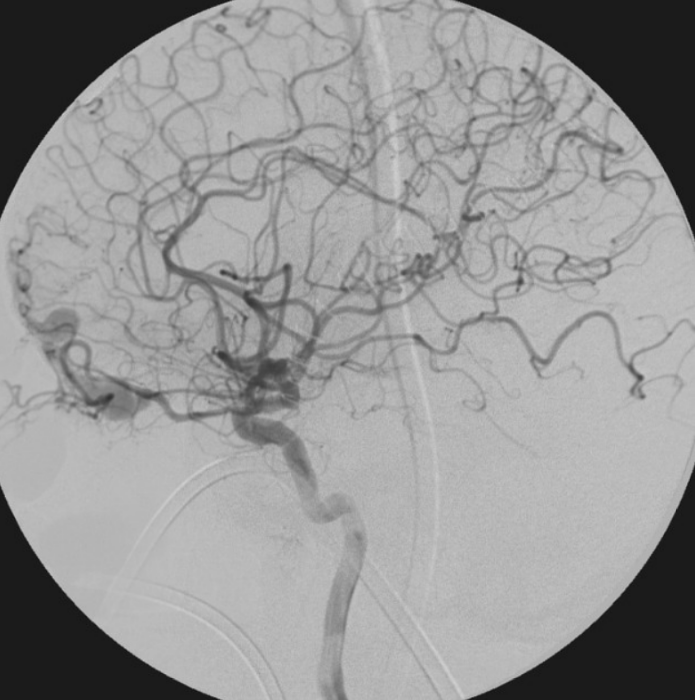

Brain DAVF (Dural Arteriovenous Fistula)

A Brain DAVF (Dural Arteriovenous Fistula) is an abnormal connection between arteries and veins located in the covering (dura) of the brain. Unlike AVM, DAVF does not have a true nidus but involves abnormal shunting into venous sinuses.

Some DAVFs are benign, while others with cortical venous reflux carry a high risk of bleeding and require urgent treatment.